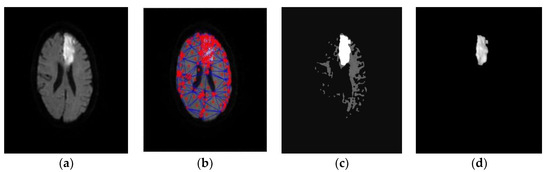

- Subudhi, A.; Acharya, U.R.; Dash, M.; Jena, S.; Sabut, S. Automated approach for detection of ischemic stroke using Delaunay Triangulation in brain MRI images. Comput. Biol. Med. 2018, 103, 116–129. [Google Scholar] [CrossRef]

| Asit et al. (2018) [114] | DWI scan | 192 images | Delaunay triangulation | Random forest | 0.93 |